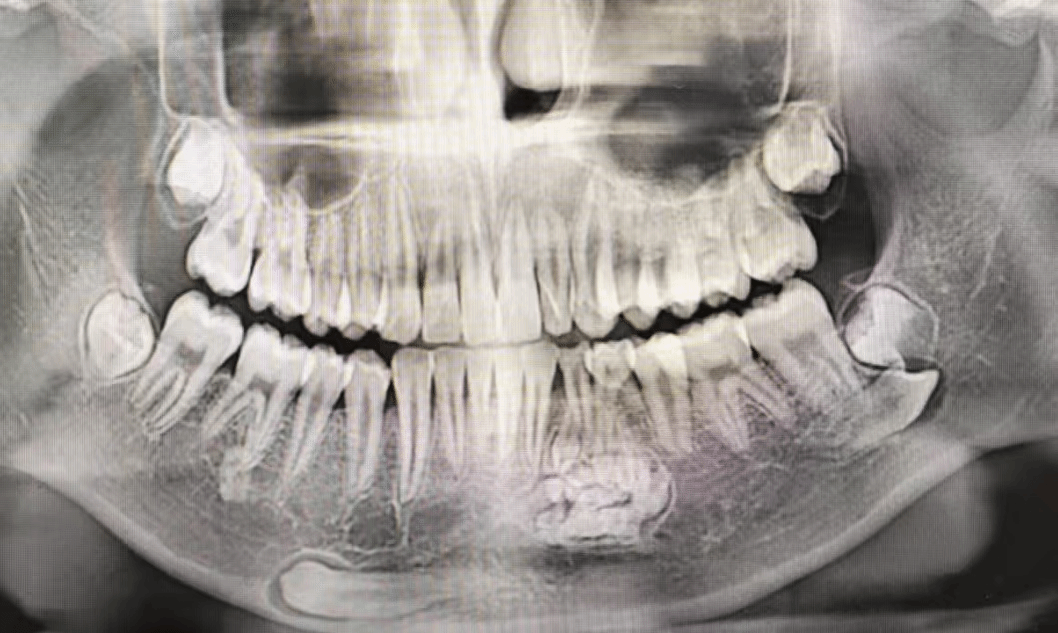

今年13岁的小海(化名)因牙齿不整齐来我院牙颌颜面发育管理中心就诊,希望通过正畸能排齐牙齿,在检查中发现他有两颗乳牙滞留,经过进一步影像学检查,揭示了他下颌骨内有牙瘤及异位埋伏阻生牙。牙瘤的出现通常伴随骨质膨隆或牙齿缺失,而异位的埋伏阻生牙则可能影响恒牙的正常萌出,因情况复杂,小海随即转至我院头颈肿瘤科接受进一步治疗。

在全面评估小海的情况后,头颈肿瘤科团队决定实施手术,手术需要医生们细致操作,确保完整摘除牙瘤组织,同时避免损伤上方牙根及周围神经,异位的埋伏阻生牙位于下颌骨关键区域,拔除过程需极其小心,避免损伤神经和恒牙胚。一切准备就绪后,手术在全麻下进行,成功摘除了形态各异的牙样组织,并完整拔除了埋伏阻生的两颗牙齿。术后小海恢复良好,未出现并发症。